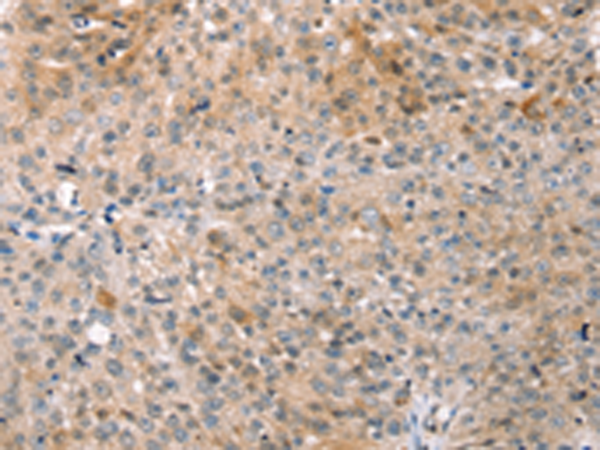

分类: 科研抗体货号: P07217别名: EB1; SCAF1; SCAFI; SIG81; COX7AR; COX7RP应用: WB,IHC反应种属: Human, Mouse

分类: 科研抗体货号: P07218别名: COX11P应用: WB,IHC反应种属: Human, Mouse

分类: 科研抗体货号: P07246别名: LIT; DCR1; TRID; CD263; TRAILR3; TRAIL-R3; DCR1-TNFR应用: IHC反应种属: Human

分类: 科研抗体货号: P07216别名: NOC4, COX4NB, C16orf2, C16orf4, FAM158B应用: WB,IHC反应种属: Human, Mouse, Rat

分类: 科研抗体货号: P07243别名: DCIR; LLIR; CD367; DDB27; CLECSF6; HDCGC13P应用: WB,IHC反应种属: Human

分类: 科研抗体货号: P07213别名: EDS4A应用: IHC反应种属: Human, Mouse, Rat

分类: 科研抗体货号: P07239别名: HLP; CP33; CP34; CYP3A; NF-25; CYP3A3; P450C3; CYPIIIA3; CYPIIIA4; P450PCN1应用: WB,IHC反应种属: Human

分类: 科研抗体货号: P07212别名: AOM; ANFH; SEDC; STL1; COL11A3应用: WB,IHC反应种属: Human, Mouse, Rat

分类: 科研抗体货号: P07237别名: AHH, AHRR, CP11, CYP1, P1-450, P450-C, P450DX应用: WB,IHC反应种属: Human, Mouse, Rat

分类: 科研抗体货号: P07211别名: 3MC2; CLK1; CL-K1-I; CL-K1-II; CL-K1-IIa; CL-K1-IIb应用: IHC反应种属: Human, Mouse